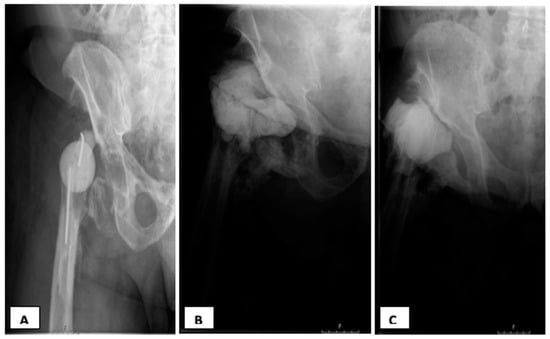

Figure 2. Hip radiographs: periprosthetic joint infection (PJI) with history of three prior debridement surgeries and systemic antibiotics. (A) First Hip spacer (Girdlestone); (B) Status post second spacer exchange (third spacer) for persistent infection; (C) Status post third spacer exchange: failure of intended reimplantation. Clinical history: First exchange occurred after recurrence of fever, elevated CRP, local signs of hip infection and positive urinalysis s/p two-weeks off antibiotics. Of note, purulence was observed during the first exchange surgery. Second Exchange occurred after a purulent drainage, with an aspiration culture growing methicillin-resistant Staphylococcus aureus (MRSA). After a third spacer exchange, the intra-operative cultures grew Klebsiella Pneumoniae.